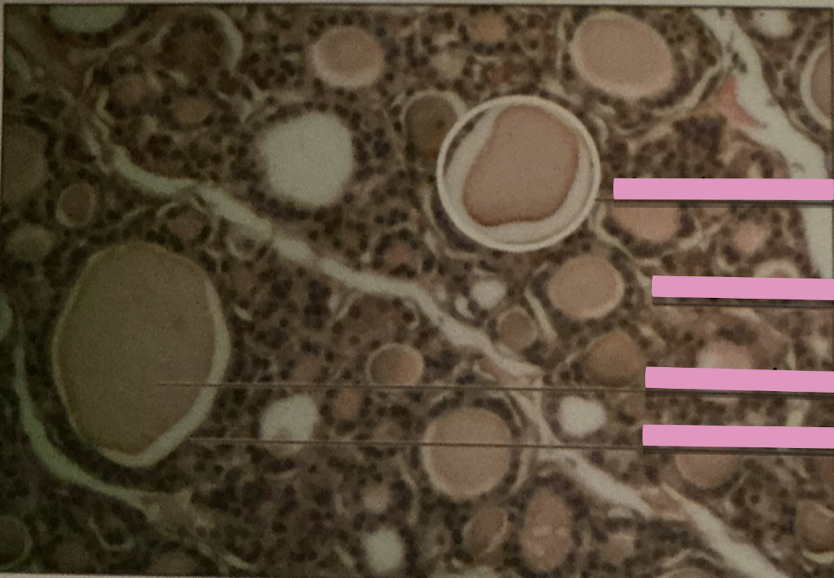

thyroid gland

thyroid gland

contain follicular cells producing thyroxine (T4) and triiodothyronine (T3) from thyroglobulin

parafollicular cells

secrete calcitonin, lower blood calcium; inhibit osteoclast, stimulate osteoblasts

thyroid and parathyroid glands

thyroid gland

bi-lobed structure that lies against & around larynx and trachea